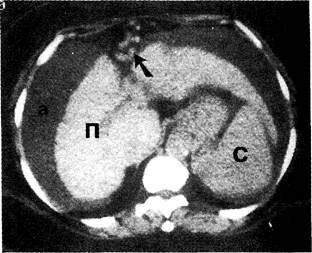

КТ диагностика тубоовариального абсцесса: Подходы и изображения

Раздел: Объективный взгляд